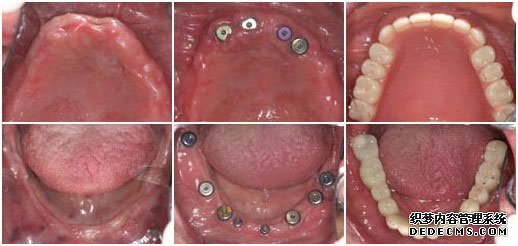

种植牙前 植入种植体后 套上烤瓷牙冠完成手术

检查:全口牙齿缺失,无能明显依托的牙根,X片显示根尖无异常

美牙方案:通过口腔数码内窥镜、口腔全景机及微创无痛设备,精密观测口腔内的状况,运用先进的瑞士ITI种植牙技术进行种植。

王老伯来武汉爱齿尔口腔就诊的时候,情况非常糟糕,在医生的检查下,发现他口腔内的牙齿全部缺失,并没有可持久依托的牙根,面对这一情况,医生只有建议王老伯做种植牙。虽说种植牙的治疗时间较长,但是对于王老伯这样的牙齿状况,种植牙是一种十分理想的选择。

由于王老伯今年已经61岁,所以在植入种植体后的恢复时间比一般人要常一些,花了将近5个月的时间才长好,但这并不影响种植牙的效果。最后在套烤瓷牙冠的时候,王老伯的家人也感到十分惊异,因为种出来的牙齿不但美观漂亮,甚至比王老伯之前的真牙还要逼真,一下子王老伯的牙齿看起来仿佛只有20多岁。而最最高兴的还是王老伯,他说:“我以前戴的全口活动假牙,吃东西不方便,连老伴弄的饭菜也都不想吃,可这次种牙太成功了,真是那句老话:‘牙好,胃口就好啊!’,太感谢你们了”